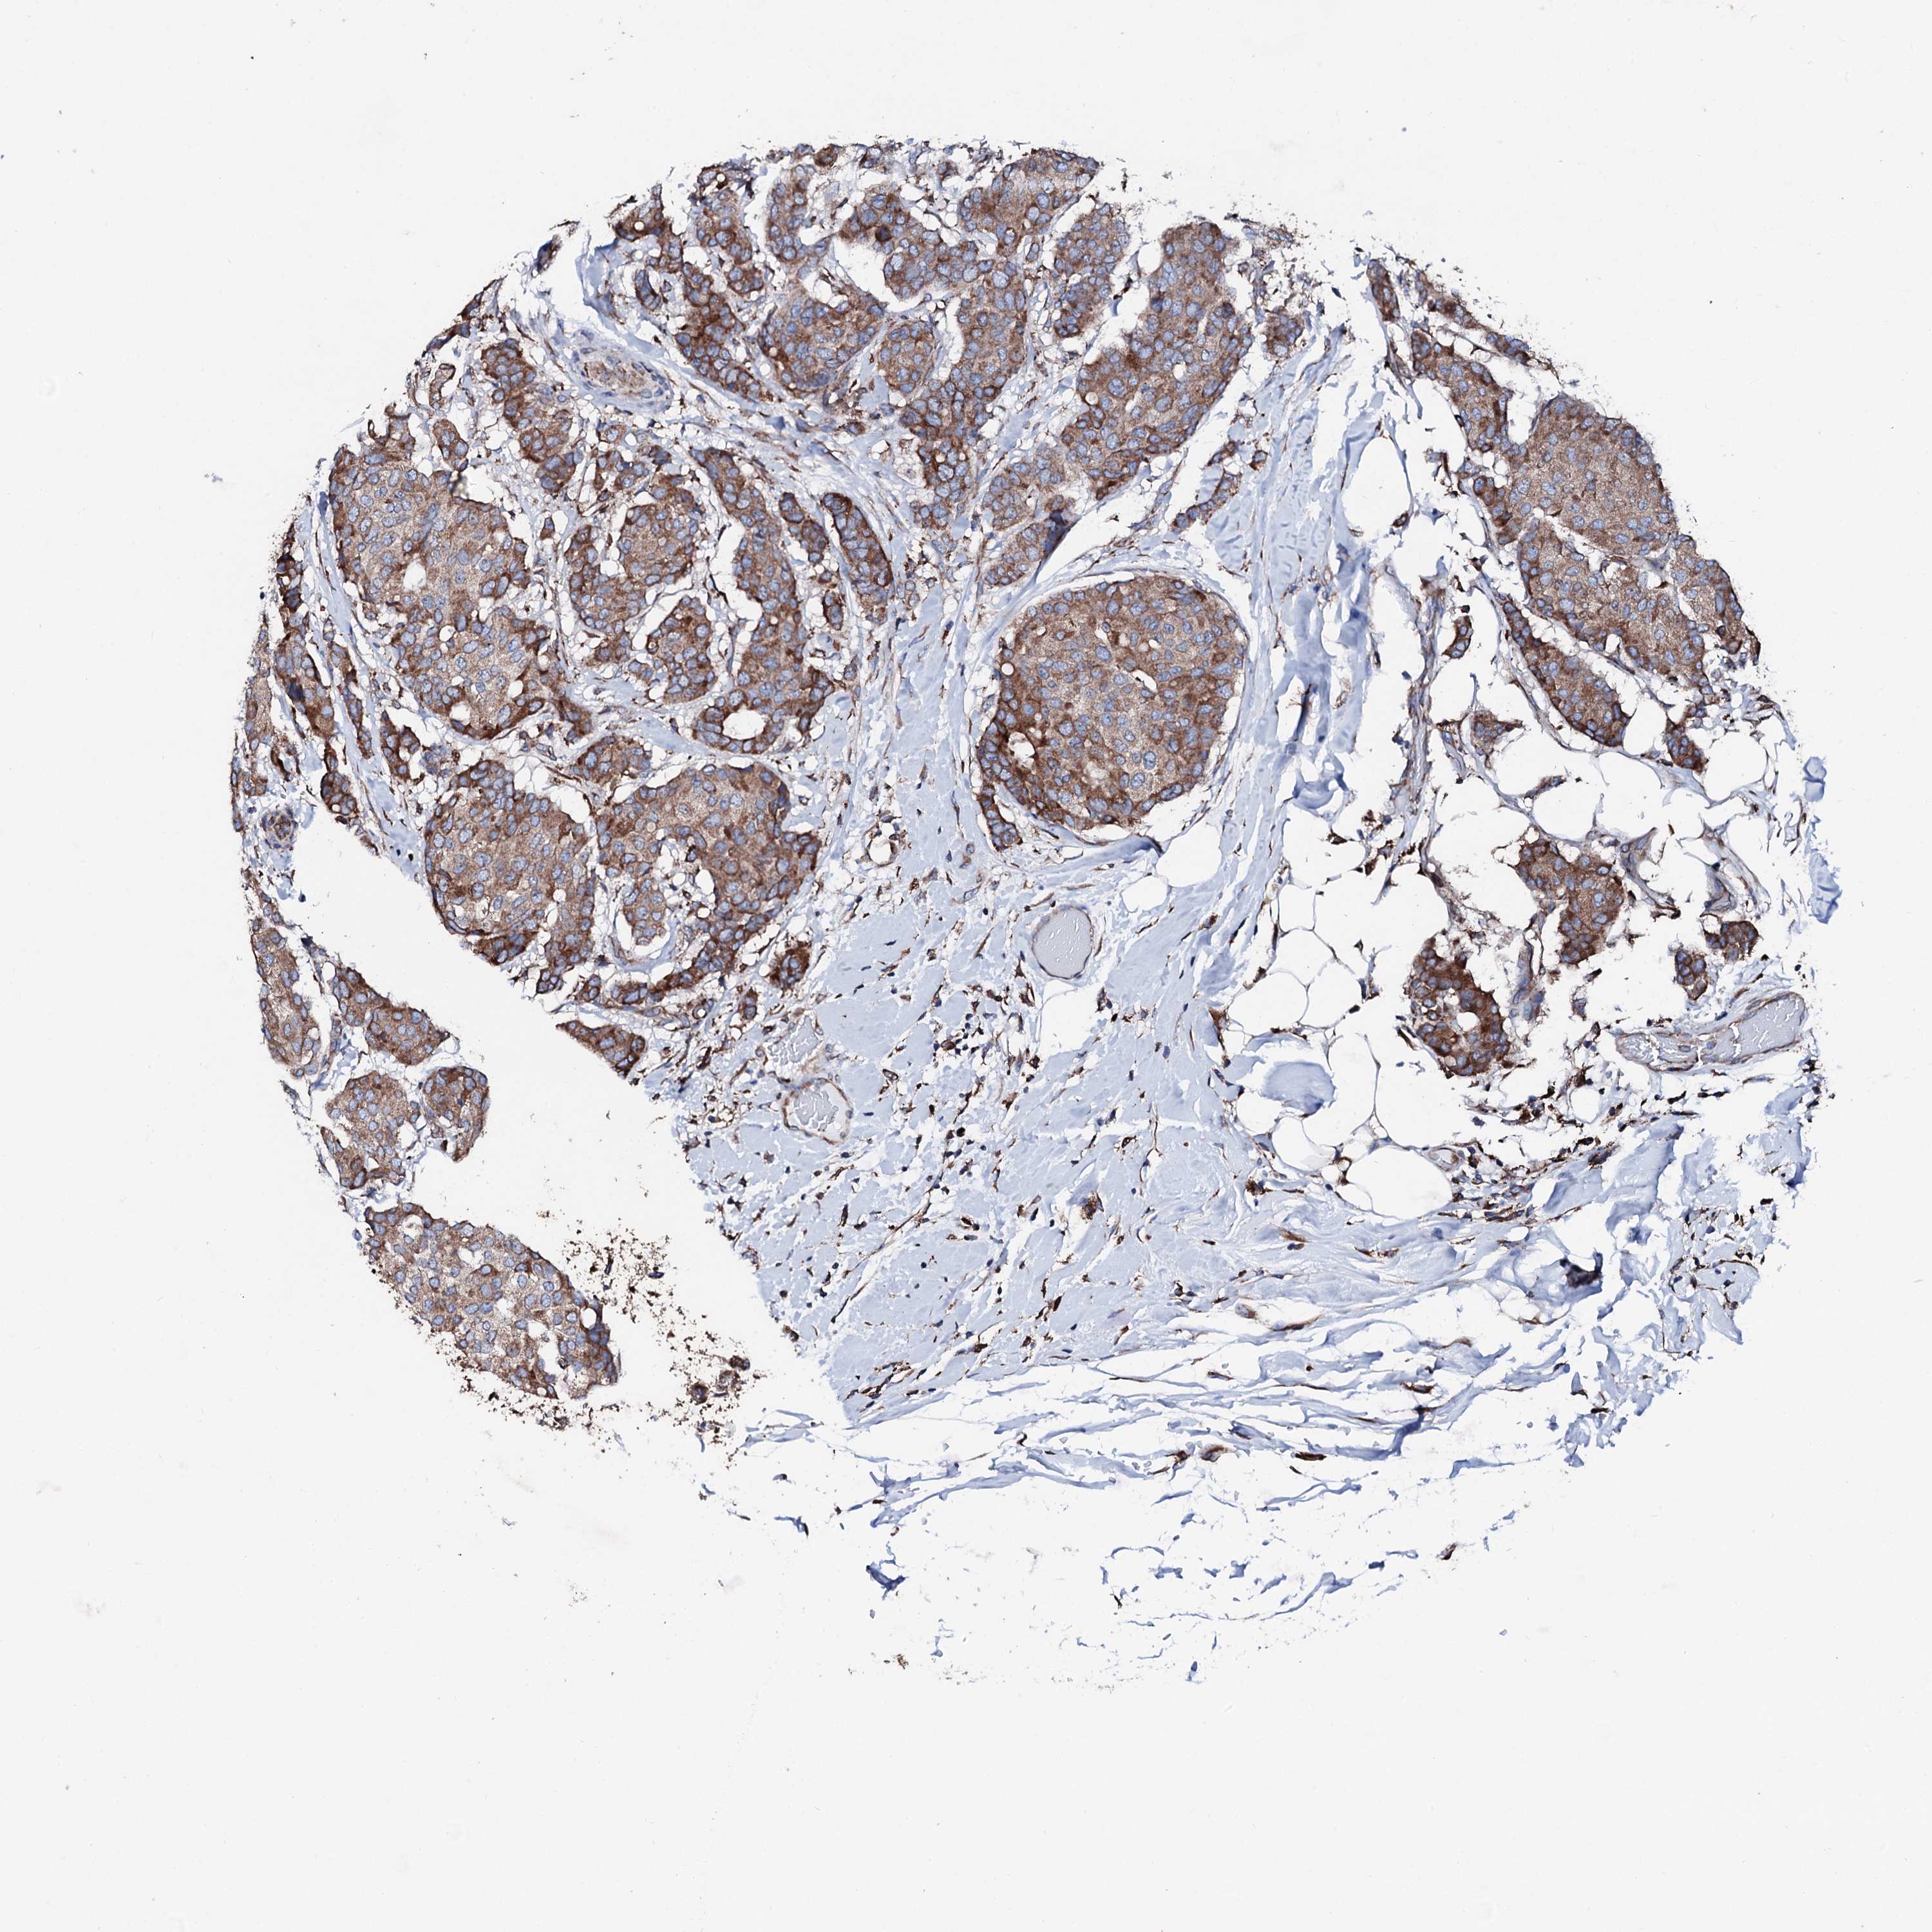

CANCER BREAST CANCER Show tissue menu

BRCA TCGA BRCA VALIDATION PROTEIN EXPRESSION